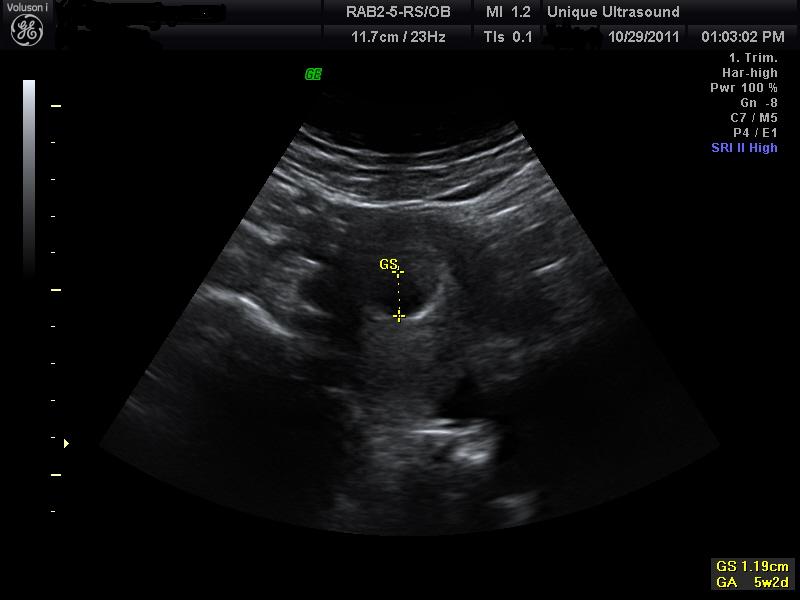

Two weeks, or just 14 days after conception a “primitive streak”, a faint white trace of the caudal, or tail end of the embryonic disk, formed by the movement of cells, providing the first evidence of the embryonic axis. This later develops into the fetus’ central nervous system. One week later, the embryo is now about 1/12 of an inch and at this point the heart begins to beat. Amazing at just 3 weeks! At the 4 week stage the embryo now looks like a small tadpole and has grown to 1/5 of an inch. By the time the embryo is 5 weeks it has developed tiny buds thus being the arms and the legs. A lot has developed in this short amount of time and at this point with an ultrasound you are able to see a small sack with a peanut shaped embryo.